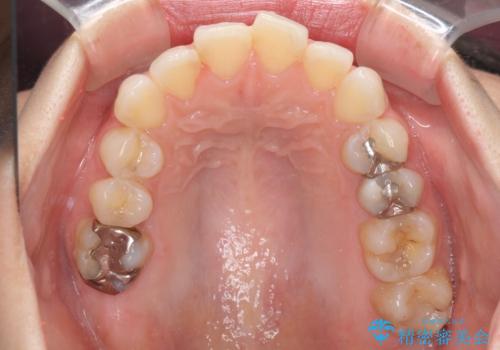

- 前歯のデコボコを気にして来院された患者様です。

主に下顎歯列全体の後方移動とIPR(歯と歯の間を削る)によってデコボコが解消するように設計し、インビザラインにより治療を行うこととしました。

舌突出癖がある方ですと、叢生が解消すると同時に前方に拡大されてしまいますが、ゴムかけをしっかりと行ってくださったこともあり、スッキリとした仕上がりとなりました。